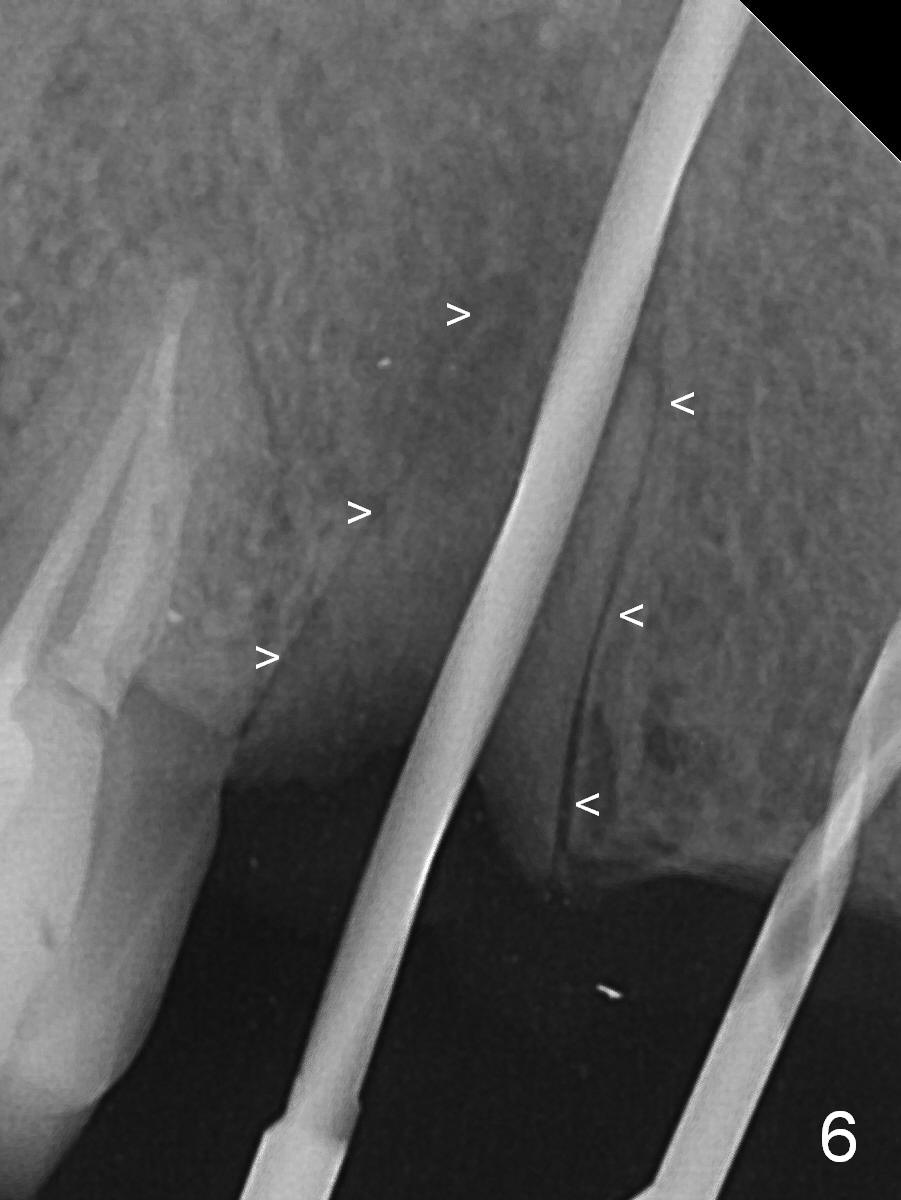

When the bridge is sectioned between #7 and 8, the tooth #6 is found non-salvageable (Fig.1). Incision shows the atrophic buccal plate at #7 (Fig.2 arrowheads); to prevent the same feature from happening at #6 with thin buccal plate, the most buccal portion of the root is preserved (socket shield (Fig.2-4: *)). The initial osteotomy is established in the palatal slope at #6 (Fig.5 circle) with 1.5 mm drill (Fig.6,7). A portion of the root is visible in Fig.6 (arrowheads). After sequential osteotomy with 2 mm, 3 mm (Fig.8) and 3.2 mm drills, a 4x15 mm implant is placed (Fig.10). To accommodate the cross bite, the coronal portion of the implant (Fig.9 white circle) is positioned close to the socket shield. It appears that the shield prevents the implant from encroaching the buccal plate.